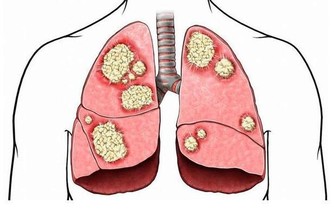

阿里巴巴董事長兼CEO馬雲在第十三屆中國企業家年會上的演講,我們相信10年以後中國3大癌症將會困擾著每一個家庭,肝癌、肺癌、胃癌。

肝癌,很多可能是因為水;肺癌是因為我們的空氣;胃癌,是因為我們的食物。

大致上,您每吃一份肉,就需要吃至少四份以上的蔬果才能平衡其帶來的酸性,加上各種輻射、污染、壓力、壞心情等也會使身體酸性化。這就是為何只有10%的人人體質是鹼性的。日本醫學博士柳澤文正用實驗證明100%的癌症患者是酸性體質;諾貝爾獎得主、德國生物化學家Otto Warburg博士認為缺氧的環境使正常細胞癌變,而體液酸化是導致缺氧的主要因素。